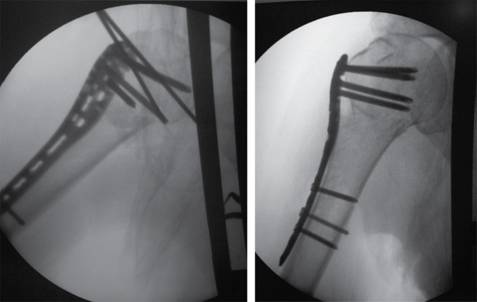

Bajo anestesia general, el paciente en decúbito supino en posición de silla de playa se inicia abordaje lateral acromial sin sobrepasar 5 cm de la punta del acromion, se diseca entre el deltoides anterior y medio, se hace disección y exposición de la cabeza humeral. Posteriormente se realiza fijación de manera percutánea con un clavo de Kirschner y se procede, bajo revisión fluoroscópica, a visualizar reducción de fractura de la metáfisis y tuberosidades (Figura 1). Se coloca placa sobre la piel ejerciendo una presión de impronta para determinar longitud y se realiza incisión distal (Figura 2). Teniendo en cuenta previa palpación y disección del nervio axilar, se desliza la placa (Figura 3) y se fija proximalmente con 3 tornillos autobloqueados en la cabeza (los tornillos más distales del implante en la posición A y B ), en algunas ocasiones se usan los tornillos de la posición C y se revisa bajo fluoroscopio reducción y posición de los tornillos y posteriormente con tornillo de cortical se adosa placa al hueso para luego colocar tornillos corticales o de bloqueo diafisarios y el tornillo de bloqueo distal (Figura 4).

El tiempo promedio de cirugía fue de 64.9 minutos (38 minutos a 124 minutos). No se reportaron complicaciones intraquirúrgicas del procedimiento, lesión del nervio axilar en el postoperatorio, conversión de osteosíntesis en ninguno de los pacientes, necrosis avascular de la cabeza humeral, ni infección en el sitio operatorio. Los resultados radiográficos revelaron 100% de consolidación de la fractura, pero evidenciaron dos pacientes con consolidación en varo (9%) y dos pacientes que mostraron cut out de los tornillos con pinzamiento de la placa con el acromion (9%) (Figura 6). Estos pacientes requirieron retiro de material de osteosíntesis por el efecto de los tornillos. El promedio de Constant score fue 68.6 (rangos: 25-94).